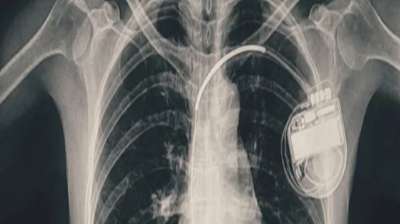

भोपाल के डॉक्टरों ने दिखाई मिसाल, हार्ट प्रॉब्लम वाली बच्ची को दी नई जिंदगी

भोपाल। भोपाल मेमोरियल अस्पताल एवं अनुसंधान केंद्र (बीएमएचआरसी) के कार्डियोलॉजी विभाग ने एक दुर्लभ और चुनौतीपूर्ण चिकित्सा उपलब्धि हासिल की है। यहां 13 वर्ष की गैस पीड़ित आश्रित बालिका को...